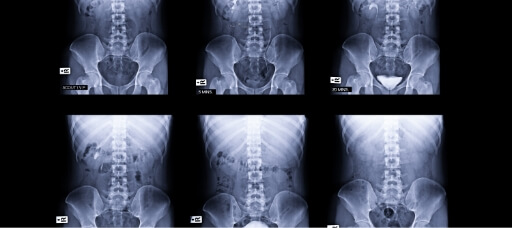

TESTING

Normalmente es necesario hacer test para poder obtener un diagnóstico preciso y acertado. Tenemos acceso a tecnología de imagen digital para visualizar el riñón.